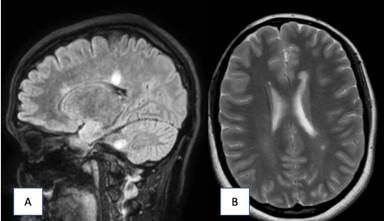

Figura 2 A) RM corte sagital secuencia FLAIR dos meses una vez iniciado el tratamiento. Se manifiesta una reducción en el número y tamaño de las lesiones localizadas en sustancia blanca. B) RM cerebral corte axial T2. Mejoría radiológica con disminución de lesiones hiperintensas presentes en sustancia blanca.

Al cabo de un mes ,se decide realizar una nueva resonancia magnética cerebral para valorar la evolución de las lesiones, en la cual persisten las lesiones de hiperseñal supra e infratentoriales previamente visualizadas, sin bien en este nuevo estudio la mayoría de ellas presentan una disminución significativa de tamaño, junto con una importante disminución del realce tras la administración de contraste paramagnético, siendo dichos hallazgos compatibles con una encefalomielitis diseminada aguda (ADEM) en proceso de resolución.